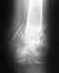

Уважаемые врачи, очень нужны советы в отношении моего голеностопа ( готова выложить все рентгены и мрт ) . в 2007 был сложный перелом в том числе и голеностоп .

Прооперировали, вставили железные пластины и болты - закипсовали - я наивно думала, что сниму гипс и побегу ведь многие ломают руки - ноги .... Гипс сняли через 4 месяца - отек в голеностопе страшенный, делаю мрт - а там уже артроз и сразу 4 степени . Ровно через год все железки убрали . Пару лет через боль еще продолжала верить в чудеса. Через три года получила 3 группу . Верю всем форумчанам кто пишет, что не может ходить ! В общем в НИИТО мне рекомендуют эндопротезирование или замыкание со штифтом . Рекомендуют уже на протяжении 5 лет . Одна сторона меня уже не может терпеть боль и соглашается на операцию, другая часть меня лезет в интернет и читает отзывы после эндопротезирований и замыканий - и от страха начинаются слезы рекой и без остановки . В общем я еще не нашла ни одного отзывы в интернете, кто счастлив после замыкания и эндопротезирования . Сейчас ситуация очень печальная - постоянные боли днем и ночью , гулять вообще не могу , таз развернуло влево, нога укоротилась на 4 см, появились серьезные изменения в позвоночнике в поясничном отделе, вес из-за отсутствия движений вырос . Сижу. пишу и не знаю что делать ?! надо соглашаться на операцию НО на какую ? Или еще раз взяться и местно - мазями - компрессами - массажами еще побороться ?!